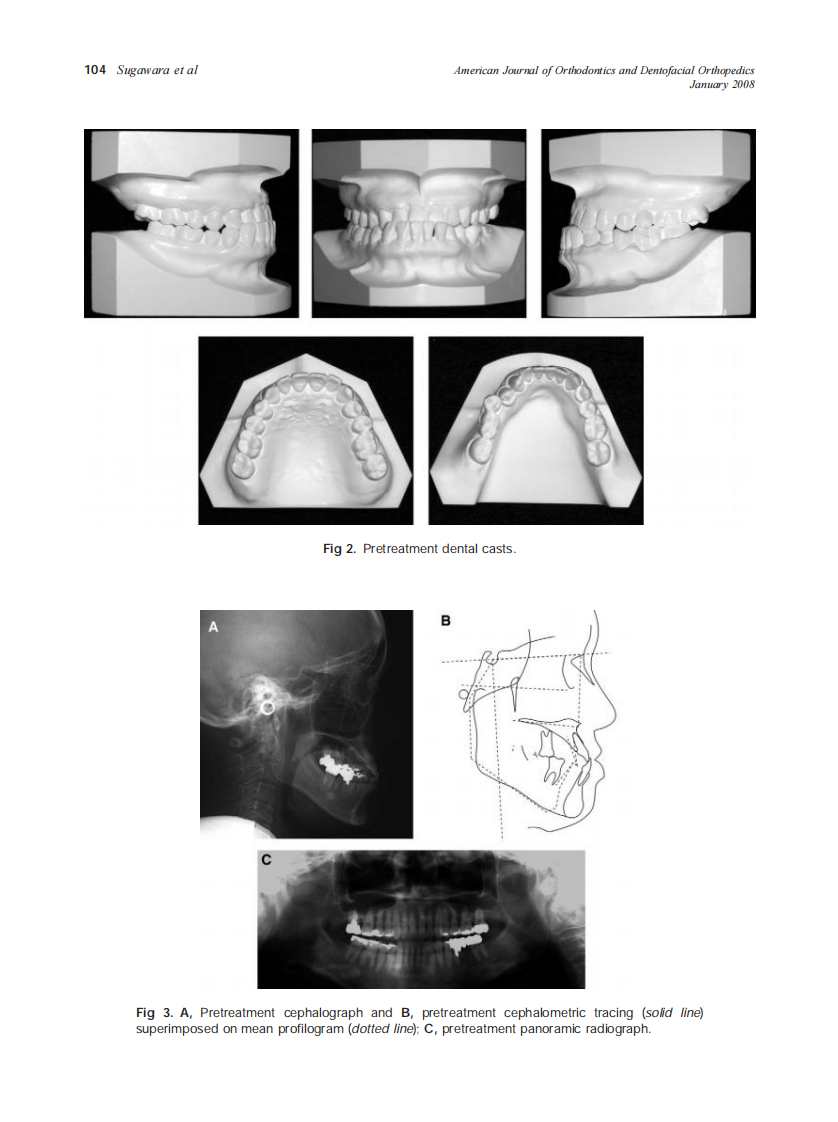

2008_133_1_102_111_Sugawara.pdf